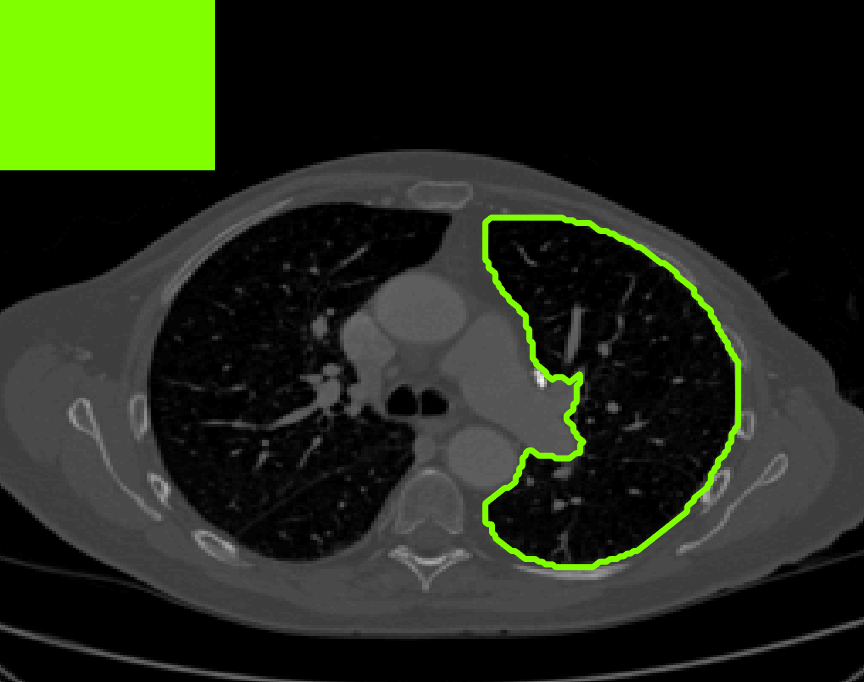

Test Images. We will perform initial tests on the images shown in Figs. 5–7. We have provided the ground truth and initialisation used for each image. Test Images 1–3 are synthetic, Test Image 4 is an MRI scan of a knee, Test Images 5–6 are abdominal CT scans, and Test Images 7–9 are lung CT scans. They have been selected to present challenges relevant to the discussion in §2. We focus on medical images as this is the application of most interest to our work. In the following we will discuss the results in terms of synthetic images (1–3) and real images (4–9). We also test the proposed approach on a larger data set of 30 CT images (a sample of which is presented in Fig. 18), comparing against existing selective methods detailed in §3.

Real Images. In Fig 12 we present results for Test Images 4–6. Here, the proposed model performs in a similar way to its competitors because these images are more typical selective segmentation problems in the sense that there is a clear distinction between the foreground and background intensities. In particular, the values in each case are: Test Image 4 , Test Image 5 , and Test Image 6 . It can be seen that the proposed model is competitive compared to previous approaches. The performance is quite poor for Test Image 5, but is arguably still the best for this challenging case. In Fig. 13 we present results for Test Images 7–9. Here the proposed model outperforms previous approaches significantly for each image. This is mainly due to the type of image considered. Specifically, the true intensities are: Test Image 7 , Test Image 8 , and Test Image 9 . The proposed model is capable of achieving results where , with other models failing completely in these cases.